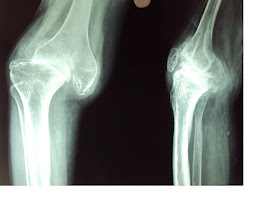

Case 1- 47 year old lady with pain. Apparently patient refused an arthrodesis

As  she is 47  an arthrodesis is the first option in view of the complexity, one may not get the best bearings and position. if insistent,  I would use possible a trabecular metal metaphyseal cone or sleeve with wedges to rebuild the lateral condyle. Tibia is standard wedge and stem.  Patella would be major realignment problem. The BAJA could be corrected  by using a smaller patellar button  superiorly. We do not have the skyline view to comment

The answer to bonegrafting question would be if at all it should be an entire distal femoral allograft shaped with a conical proximal( Red Triangle) end jammed into the  host metaphysis and protected with a by pass long stem( green line) as simple lateral condyle reconstruction alone is prone to resorption in the  short to medium term. Even the method I described from elsewhere is prone to fractures and resorption in the medium term. You could argue that one wants to rebulit the bone.